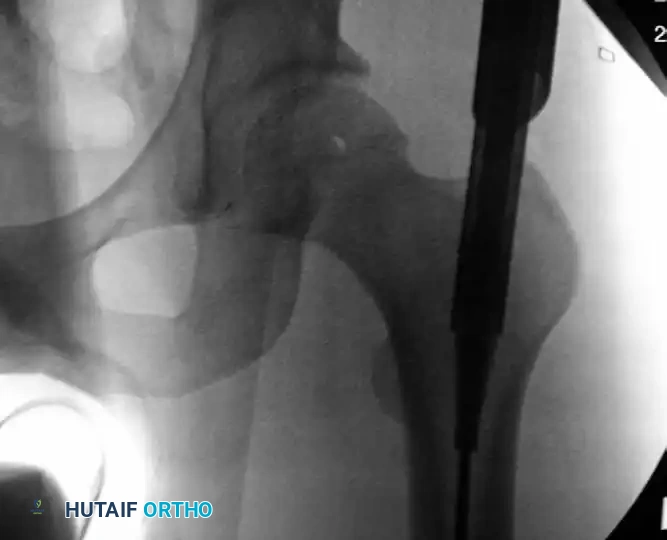

Image

Insertion of the channel reamer into the proximal femoral metaphysis to create a robust starting portal for antegrade nailing.

Ream the proximal femur until the assembly bottoms out on the entry portal tool. Continuously verify the trajectory with AP and lateral fluoroscopy to prevent posterior cortical blowout. Once the proximal channel is established, remove the entry reamer and guidewire, leaving the entry portal tube in place.

Clinical Pearl: For simple diaphyseal fractures, a standard cannulated entry reamer may suffice. However, for subtrochanteric fractures, the channel reamer is invaluable for externally controlling the characteristic flexion, abduction, and external rotation deformity of the proximal fragment.